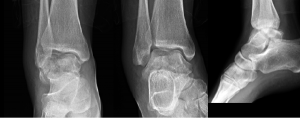

Case 1

Photos: Arun Sayal, MD, CCFP(EM)